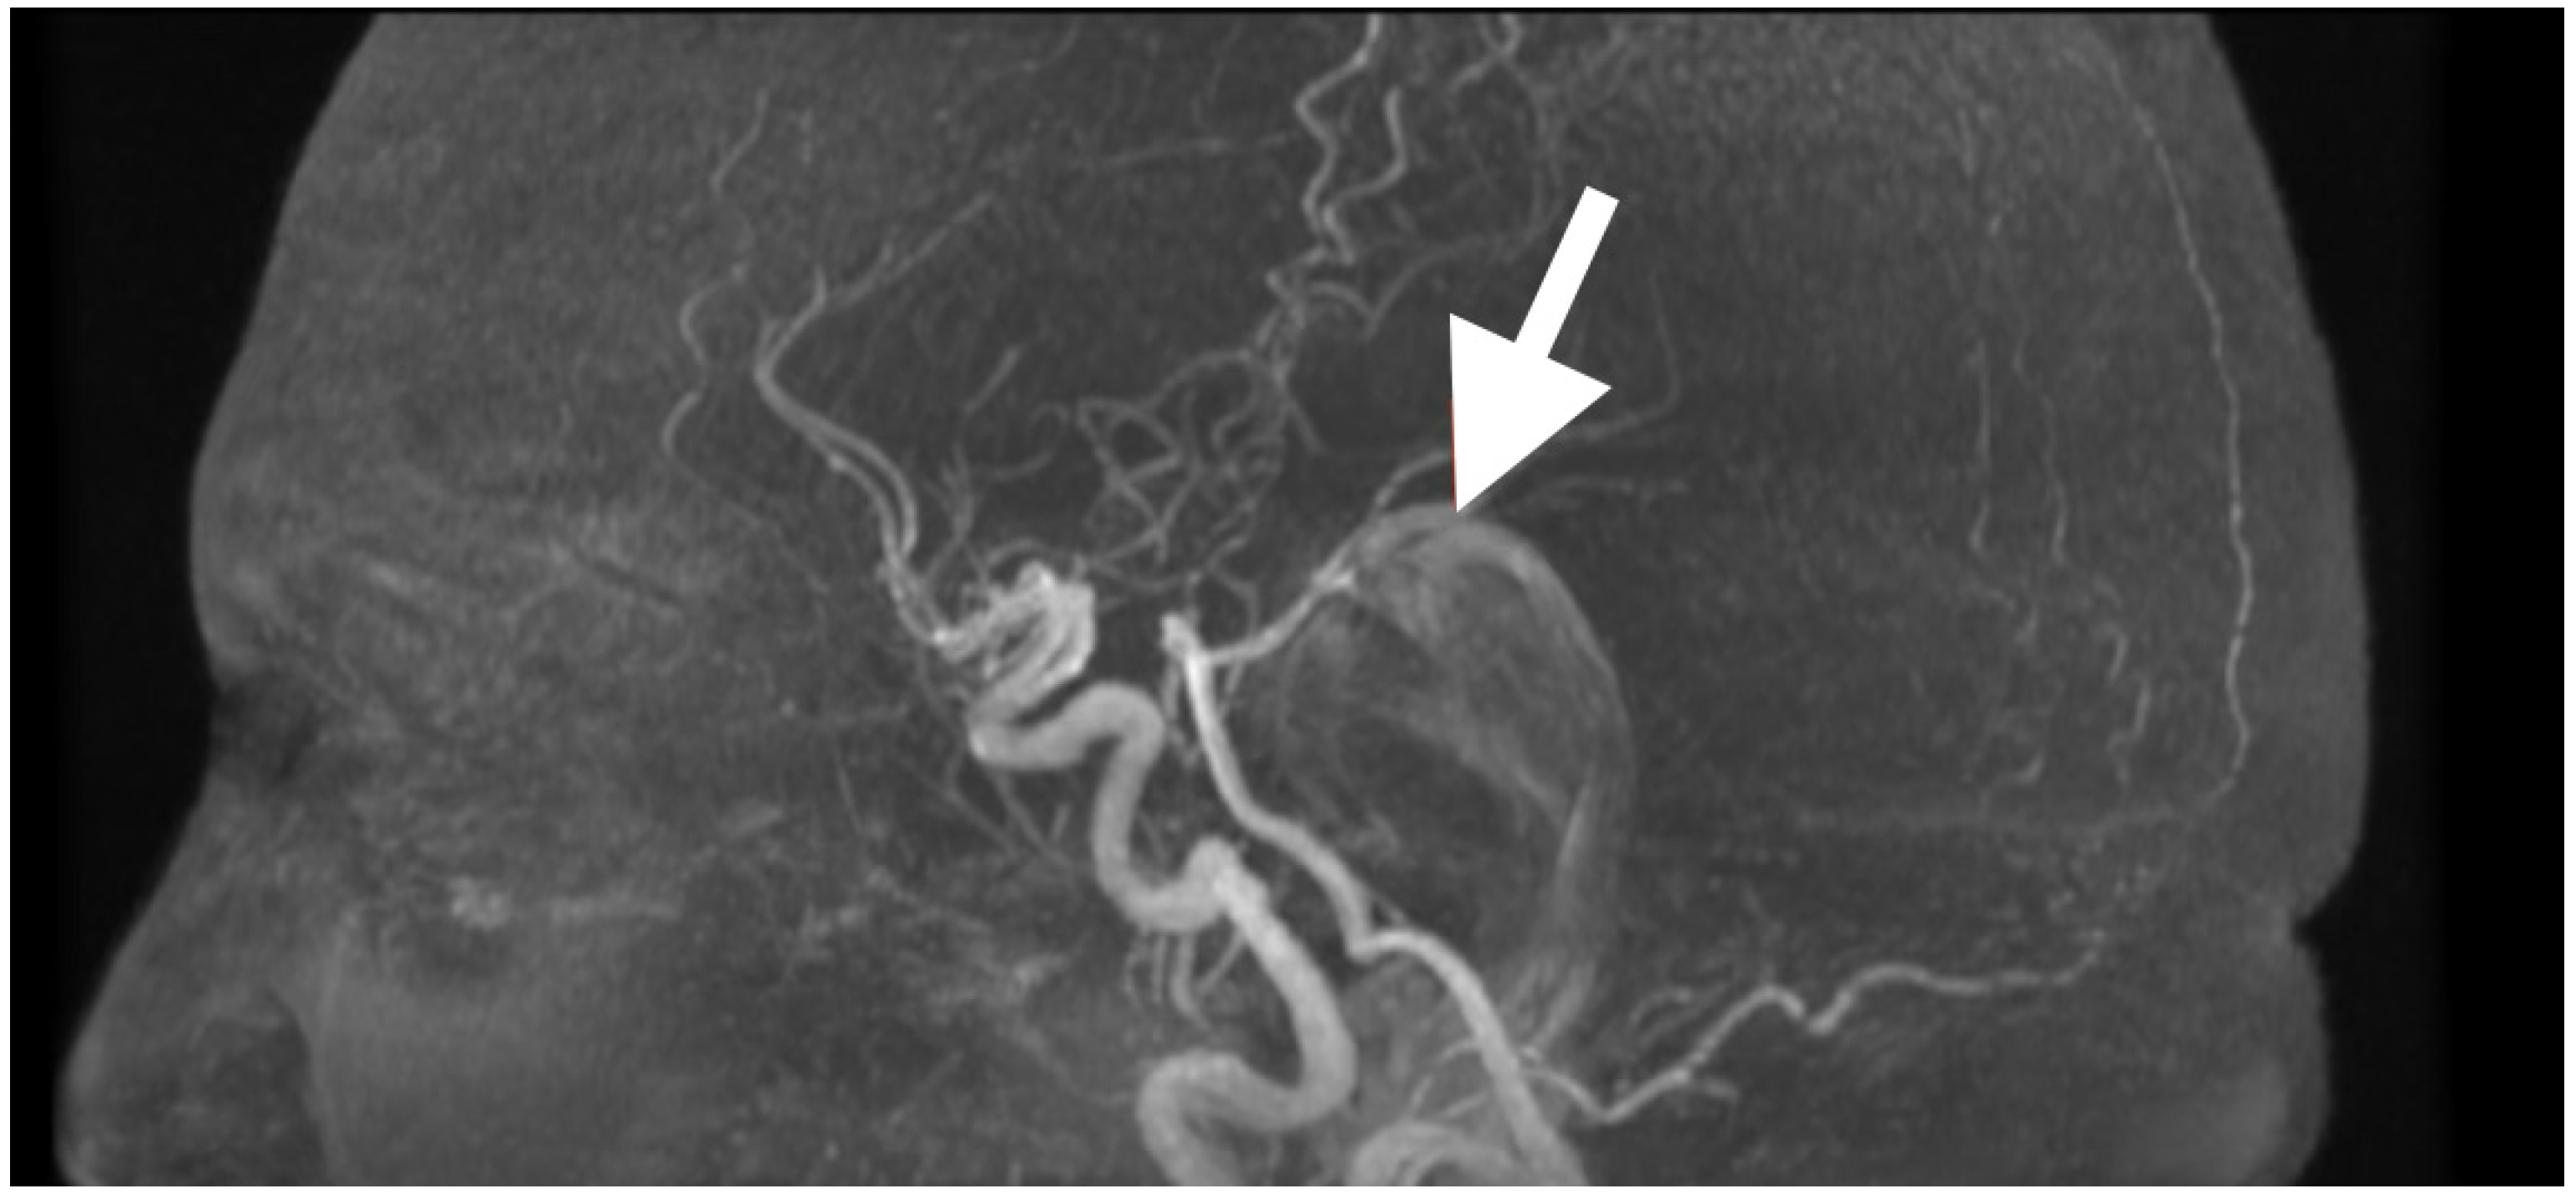

Axial T2-weighted sequences (Figure 2A,B) revealed a large, lobulated mass occupying most of the left cerebellar hemisphere, insinuating between folia and extending across the midline into the inferior vermis. The lesion was markedly hyperintense compared to cerebellar parenchyma, with internal heterogeneity suggesting layered keratinaceous content. The inferior pole of the mass descended into the cisterna magna, and its medial aspect encroached on the fourth ventricle, partially effacing it and displacing its floor anteriorly over the dorsal medulla. This displacement explained the patient’s severe truncal instability, as vermian compression interrupts integration of proprioceptive and vestibular input, and also her left-sided appendicular ataxia, arising from disruption of cerebellar hemispheric coordination pathways projecting through the dentate nucleus and superior cerebellar peduncle.

Susceptibility-weighted imaging (Figure 2C) showed tiny punctate hypointense lesions foci within lesions, suggestive of microcalcifications or hemosiderin secondary to chronic contact with the tentorium, vasculature, and pia, all indicating a long-standing, slowly growing mass. Post-contrast T1-weighted imaging (Figure 2D) displayed no enhancement, considering both lesions were different from a meningioma, hemangioblastoma, or metastasis. Coronal T2-weighted sequences (Figure 2E) demonstrated inferior and lateral extension to the foramina of Luschka, stenosing the lateral recesses of the fourth ventricle and displacing the cerebellar peduncles, most notably left. This accounted for the gaze-evoked nystagmus and pursuit deficits, considering vestibulocerebellar input and flocculonodular output. Cerebellomedullary junctional contact was responsible for the subtle bulbar discoordination secondary to pressure to the dorsal medulla near the nucleus ambiguus. Sagittal FLAIR (Figure 2F) showed an anteriorly displaced brainstem; however, the dorsal medulla was compressed against the wall of the fourth ventricle, with the pontomedullary junction displaced anteriorly. The prepontine cistern was partly effaced, and the basal cisterns were narrowed but still patent; however, inferior edema was enough for acute obstructive hydrocephalus.

Overall, the clinical–imaging cumulative data provided support for the diagnosis of an extra-axial, slow-growing epidermoid cyst, with lobulated margins, displacing the subarachnoid space, non-enhancing, and displacing chronic vessels. The MRI-clinical correlation was telling—compression via the vermis for truncal ataxia, hemispheres for dysmetria and dysdiadochokinesia, peduncles for pursuing instability, and medulla for bulbar signs. Severe compression of the fourth ventricle and effacement of the cisterns defined surgical urgency and targets that day.

Figure 2. Preoperative magnetic resonance imaging of the posterior fossa. (A,B) Axial T2-weighted images reveal a large lobulated hyperintense lesion occupying the left cerebellar hemisphere, extending medially into the vermis and inferiorly into the cisterna magna, with partial effacement and anterior displacement of the fourth ventricle. The lesion insinuates between cerebellar folia without a discrete capsule, a feature characteristic of epidermoid tumors. (C) Susceptibility-weighted imaging shows punctate hypointense foci within the lesion, likely representing calcific or hemosiderin deposits from chronic contact with adjacent neurovascular structures. (D) Axial post-contrast T1-weighted image demonstrates absence of enhancement, distinguishing the lesion from hypervascular posterior fossa neoplasms. (E) Coronal T2-weighted image depicts inferior extension toward the foramen of Luschka and compression of the cerebellar peduncles, explaining the patient’s gait instability, gaze-evoked nystagmus, and dysdiadochokinesia. (F) Sagittal FLAIR sequence confirms anterior displacement and flattening of the dorsal medulla with partial effacement of the prepontine cistern, correlating with the subtle bulbar incoordination observed on examination.